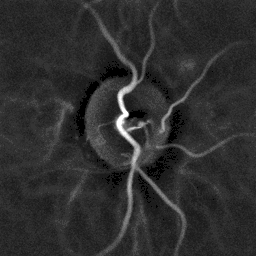

- In een later stadium ontstaan microaneurysmata, vlamvormige bloedingen, puntbloedingen en zogenaamde "cotton wool spots". Dit zijn ischemische veranderingen die aangeven dat er niet meer genoeg zuurstof op deze plekken in het netvlies komen. Exsudaten van bloedplasma, ophoping van subretinaal vocht kunnen macula-oedeem veroorzaken.

- Graad 4: zeer ernstige hypertensieve retinopathie met verschijnselen van graad 3 + zwelling van de papil (papiloedeem).